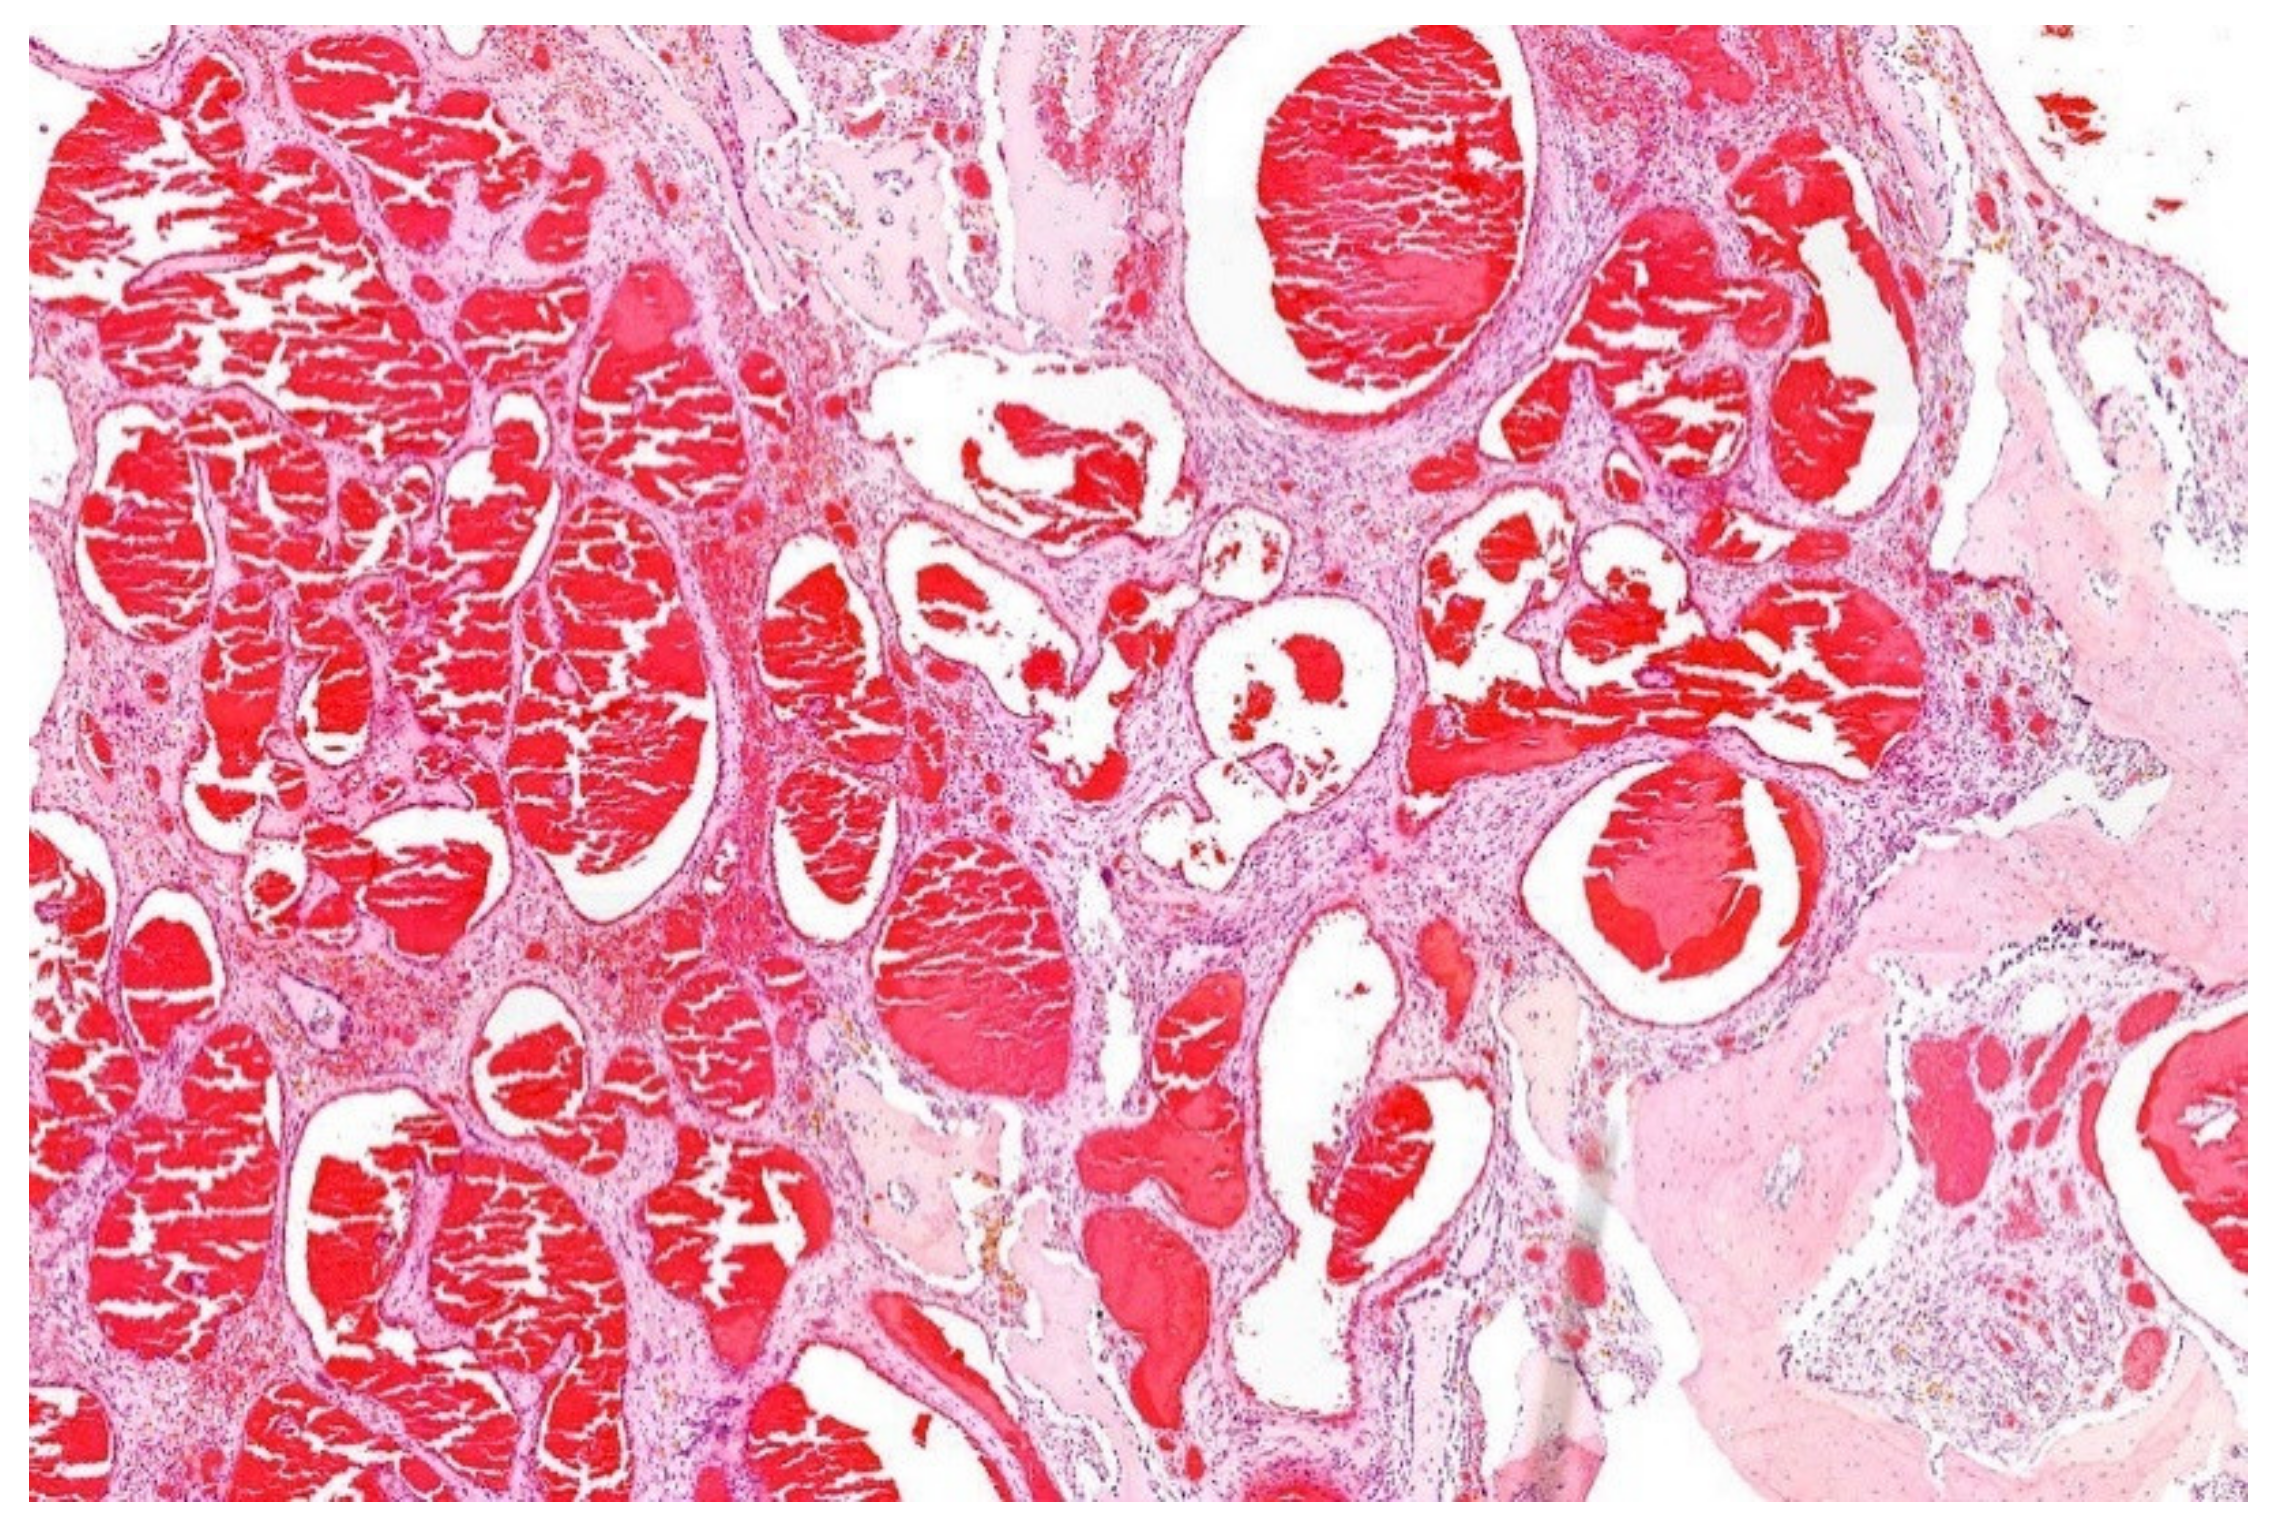

13. Hemangioma of Bone with an EWSR1-NFATC1 Fusion